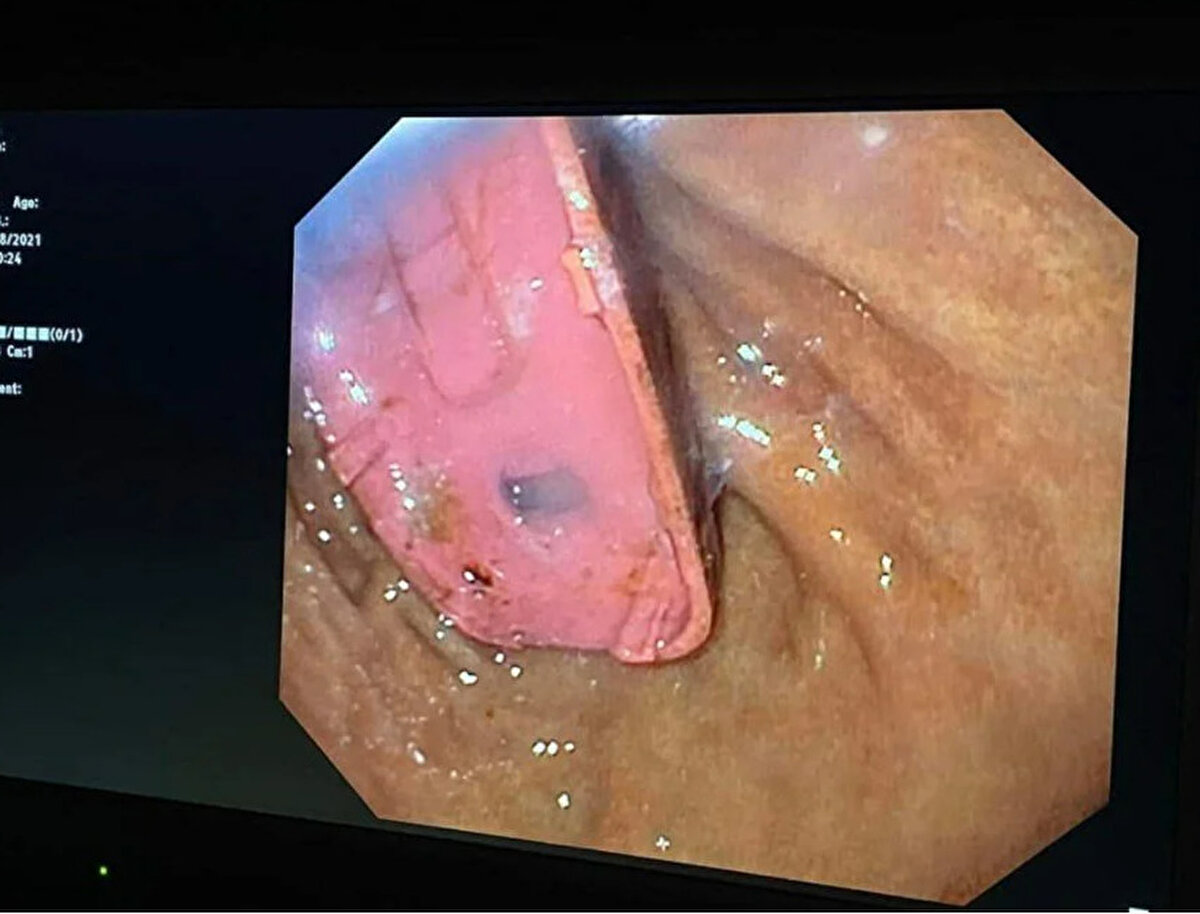

Güneydoğu Avrupa'da denize kıyısı olmayan bir ülke olan Kosova'nın başkenti Priştine'de doktorlar, Nokia 3310 model bir cep telefonunu yutan adamı ameliyat etti. Telefonun adı açıklamayan adamın midesinde dört gün kaldığı belirtildi. Başarılı operasyonu gerçekleştiren sağlık ekibinin başındaki doktor Skender Teljaku, adamın midesinden çıkarılan telefonun fotoğrafları ile röntgen ve endoskop görüntülerini Facebook'ta yayınladı.

Teljaku yaptığı açıklamada, tıbbi ekibin telefonu mideyi kesmeden, endoskop olarak bilinen özel cihazlar kullanarak üç ayrı parçaya ayırmayı başardığını söyledi. Teljaku, ayrıca yaklaşık iki saat süren işlem sırasında "herhangi bir komplikasyon" yaşanmadığını sözlerine ekledi. Bununla birlikte 33 yaşındaki adamın telefonu yuttuktan sonra yaşadığı acı nedeniyle Kosova'nın başkentindeki hastaneye gitmeye karar verdiği aktarıldı. Teljaku, özellikle bataryanın en tehlikeli parçası olduğunu, patlayarak hayatı potansiyel olarak tehlikede olan adamın bağırsaklarına kimyasal salabileceğini söyledi.